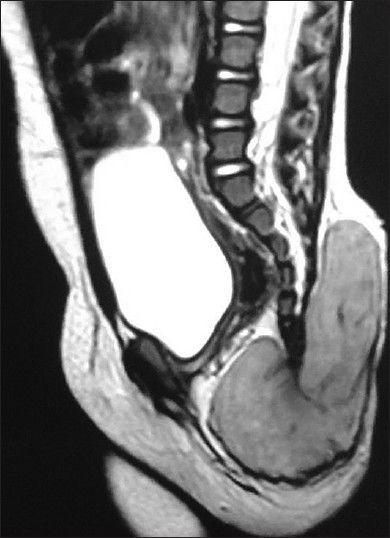

Primary localized congenital sacrococcygeal neuroblastomas (SCNs) are rare. Diagnosis is based on histological and immunohistochemical evaluation, which is indispensable not only for determining tumor type but also for predicting biological behavior. We report a rare case of congenital SCN in a 9-month-old baby girl. Based on clinical and radiological findings, a provisional diagnosis of solid variant of sacrococcygeal teratoma (SCT) was made. The swelling was entirely excised. On histopathological examination, diagnosis of neuroblastoma, differentiating type in the sacrococcygeal region was considered. On immunohistochemistry, the tumor cells showed immunoreactivity for markers such as neuronspecific enolase, chromogranin-A, synaptophysin, and cyclin D1. S-100 showed positive cytoplasmic immunoreactivity. CD99, leucocyte common antigen, PanCK, and epidermal growth factor receptor were nonreactive. Cyclin D1 showed strong nuclear immunoreactivity. p53 was negative and Ki67 labelling index was less than 1%. The immunohistochemical markers studied, confirmed the histopathological diagnosis, and the cell proliferative index markers indicated it to be a very low grade lesion. Postoperatively, the child is disease-free and has achieved normal milestones for age for period of 6 months.